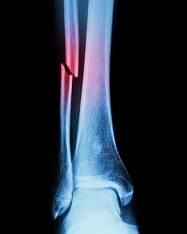

Calf, Ankle, Foot — Live Webinar